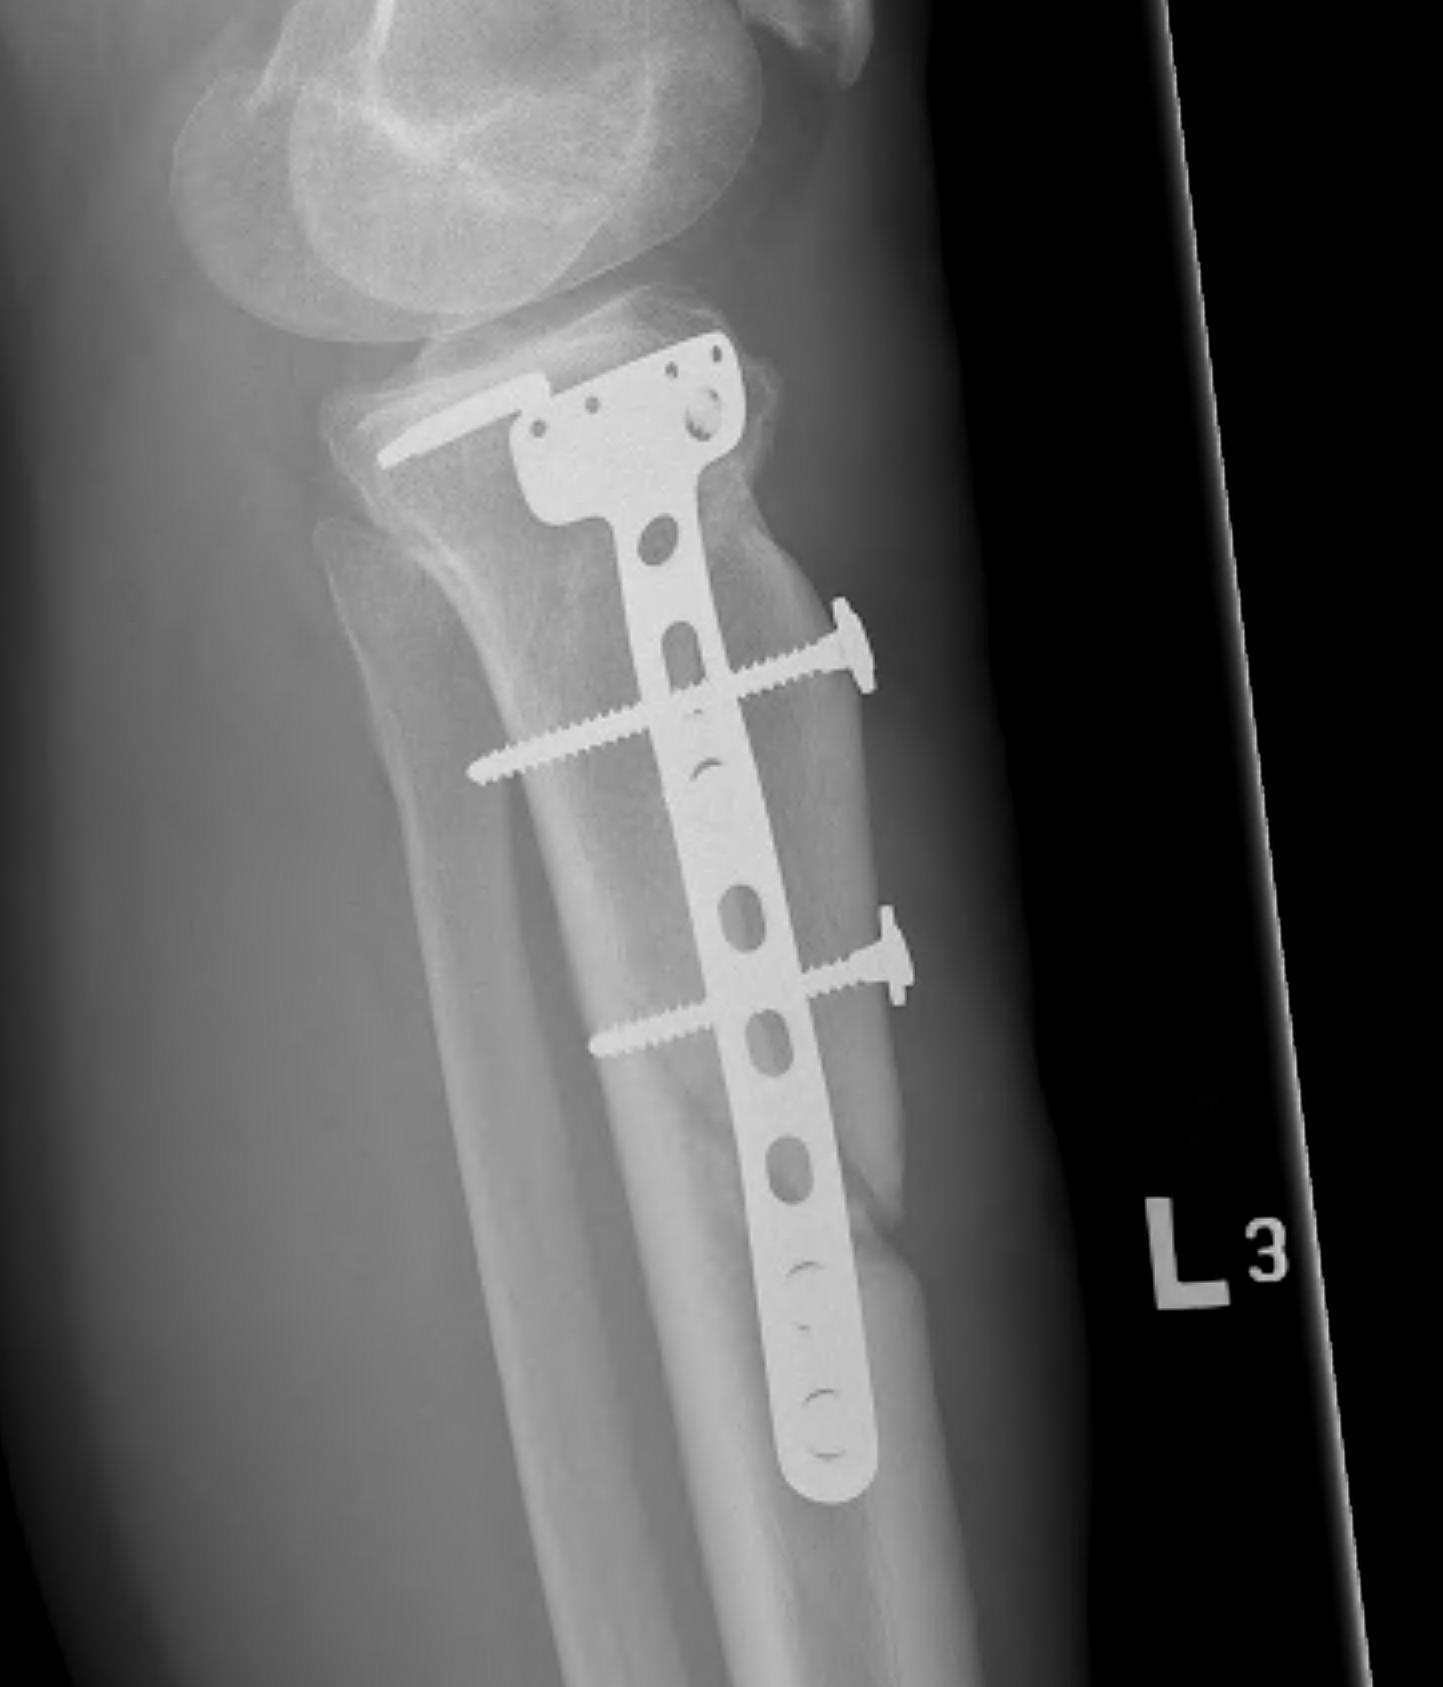

Parosteal Osteosarcoma distal femur

A. Hemicortical resection and posterior hemicortical allograft reconstruction

- hemicortical resection and hemicortical allograft reconstruction

- 111 cases (18 parosteal, 37 adamantinoma)

- 18% host bone fracture

- 7% nonunion

- 7% infection

- 3% allograft fracture